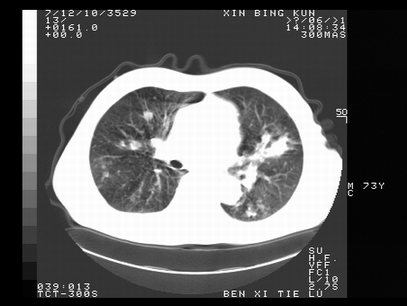

标题: CT10820:男,73岁,病史肺TB,现病史肺炎,直肠CA术后 [打印本页]

标题: CT10820:男,73岁,病史肺TB,现病史肺炎,直肠CA术后

双肺间质改变,依据病史双肺多发结节灶考虑转移,少量胸水.

1.两肺结核.2.两肺多发转移瘤.3右侧少量胸腔积液4.主动脉钙化.

双肺多发结节及条片状致密影,右侧少量胸腔积液。临床:直肠ca术后,肺tb病史。综合考虑:1 双肺转移!2 继发性肺结核合并感染!

此人病史较复杂,原有肺结核,直肠癌术后。肺部病灶形态亦呈多形性。因此,不可仅以一种病来解释肺部的病变。双肺多发的类圆形结节灶,结合病史还是首先考虑转移瘤,而双肺其余病灶还需结合化验室检查,结核或肺部感染在无其它检查资料的情况下不好排除。还是那句话----放射科医生不是开照像馆的,我们也是医生,看片一定要多结合临床及其它检查资料。要当一名合格的放射科医生,并不比当一名临床医生容易,我们可别把自已不当医生看。

两肺多发结节影,并见滋养动脉与其相连,考虑 两肺转移. 右侧胸腔积液考虑胸膜转移.

左肺上叶下叶背段,右肺中下叶见多发斑片状、条索状高密度影,兵变周围小结节影形成“树芽”样改变。 左肺上叶舌段近前胸壁处及右肺中叶内侧段见结节影。右侧胸膜腔内见液体密度区。纵隔内未见明确增大淋巴结。考虑左肺上叶舌段近前胸壁处及右肺中叶转移瘤可能性大。两肺继发型肺结核。右侧胸腔积液。